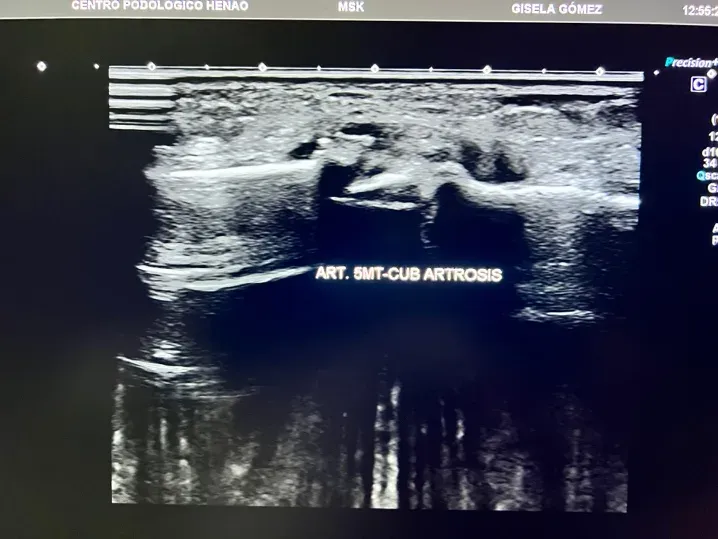

En el pie, la artrosis tiene predilección por determinadas articulaciones:

- Articulaciones del mediopié: afectan a la zona central del pie y pueden limitar actividades tan básicas como caminar en terreno irregular o subir cuestas.

Lo que la ecografía sí detecta en fases tempranas

La ecografía musculoesquelética cambia por completo esta situación. Es una herramienta de diagnóstico por imagen que permite visualizar los tejidos blandos y las superficies articulares en tiempo real, sin radiación y con el paciente en la propia consulta.

En el contexto de la artrosis del pie, la ecografía detecta:

- Cambios en el cartílago articular: antes de que la radiografía muestre nada

- Irregularidades en la superficie articular: signos tempranos de desgaste

- Inflamación articular (sinovitis): presencia de líquido o engrosamiento de la membrana sinovial

- Derrame articular: acumulación de líquido dentro de la articulación

- Osteofitos en fases iniciales: formaciones óseas que aún no son visibles en radiografía

- Estado de los tejidos blandos periarticulares: cápsula, ligamentos, tendones adyacentes